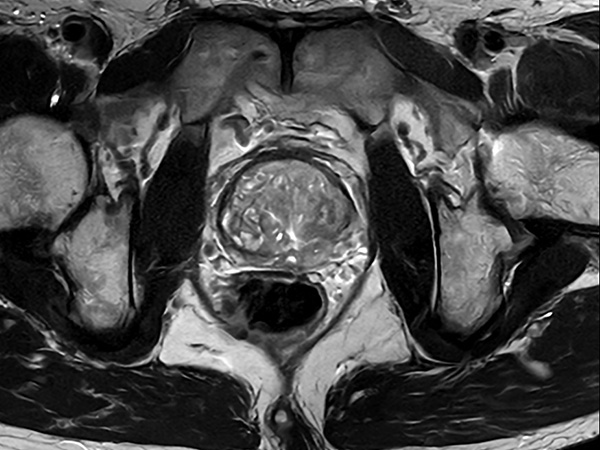

Fast Prostate imaging with SmartSpeed Precise

Kumamoto Chuo Hospital Japan